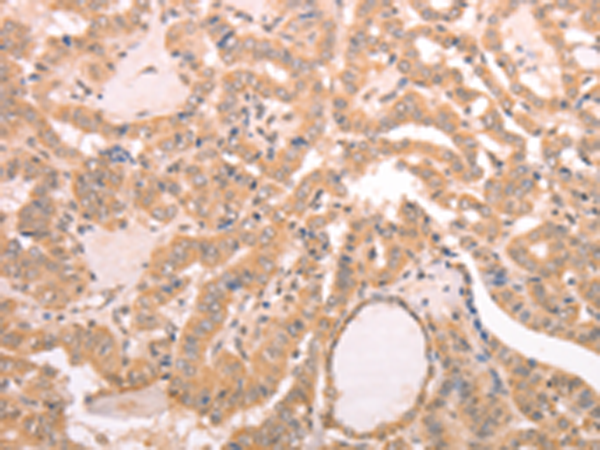

分类: 科研抗体货号: P07679别名: RNF84; MGC:39780应用: IHC反应种属: Human, Mouse

分类: 科研抗体货号: P07698别名: CMM8; OCA1A; OCAIA; SHEP3应用: WB,IHC反应种属: Human, Mouse

分类: 科研抗体货号: P07714别名: PSA; PROS; PS21; PS22; PS23; PS24; PS25; THPH5; THPH6应用: IHC反应种属: Human

分类: 科研抗体货号: P07697别名:应用: WB,IHC反应种属: Human, Mouse

分类: 科研抗体货号: P07712别名: NR1I1; PPP1R163应用: IHC反应种属: Human, Mouse, Rat

分类: 科研抗体货号: P07696别名: LGR3; CHNG1; hTSHR-I应用: IHC反应种属: Human

分类: 科研抗体货号: P07709别名: BMR2; PPH1; BMPR3; BRK-3; T-ALK; BMPR-II应用: IHC反应种属: Human, Mouse

分类: 科研抗体货号: P07695别名: TSG10; VPS23应用: IHC反应种属: Human, Mouse, Rat

分类: 科研抗体货号: P07706别名: FHL5; UNC18B; Hunc18b; UNC18-2; pp10122; MUNC18-2应用: WB,IHC反应种属: Human, Mouse, Rat

分类: 科研抗体货号: P07727别名: LYS2; LYS5; CGI-80; AASD-PPT应用: WB,IHC反应种属: Human, Mouse, Rat